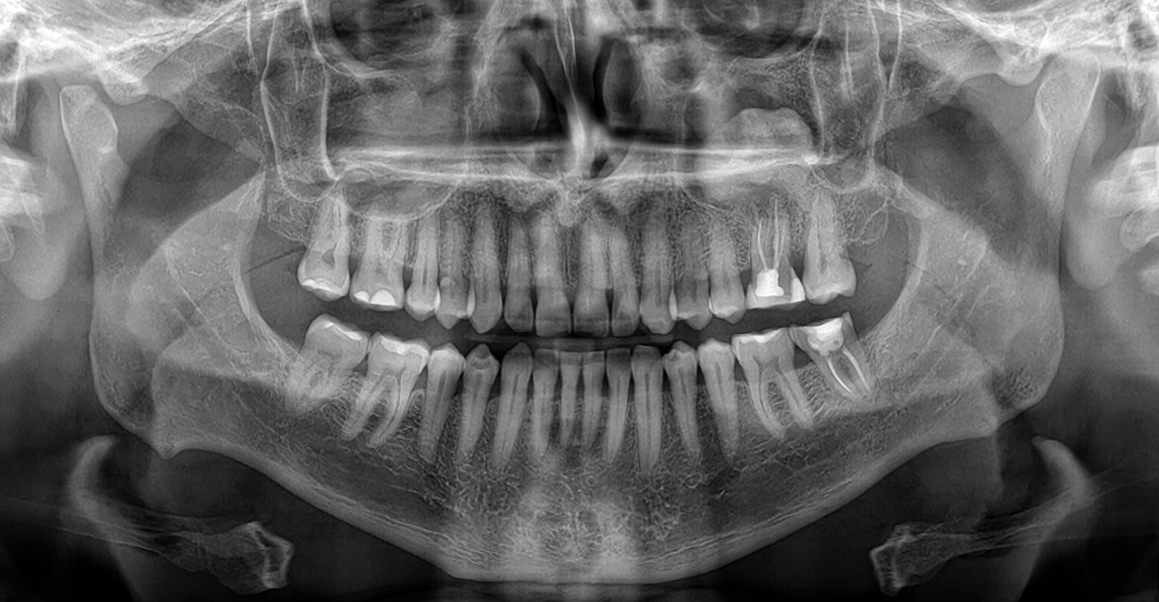

Caso Clínico N°753: FRACTURA MANDIBULAR

Casos Radiográficos

Caso Clínico N°752: OSTEOFITO

Caso Clinico Nº 751 RINOLITO (PROBABLE)

Caso Clinico N° 750 OSTEOMA PERIFERICO

Caso Clinico N° 749 EVALUACIÓN DE ODONTOMA COMPUESTO

Caso Clinico N° 748 EVALUACIÓN DE FISURA PALATINA UNILATERAL

Caso Clinico N° 747 GRANULOMA CENTRAL DE CÉLULAS GIGANTES (PROBABLE)

Caso Clinico N° 746 PROBABLE QUISTE ÓSEO SIMPLE

Caso Clinico N° 745 EVALUACIÓN DE PROBABLE OSTEOMA EN EL SENO MAXILAR

Caso Clinico N° 744 PROBABLE MICROSOMÍA HEMIFACIAL

Caso Clinico N° 743 CANINOS RETENIDOS

Caso Clinico N° 742 TERCEROS MOLARES IMPACTADOS

Caso Clinico N° 741 FRACTURA CORONO RADICULAR

Caso Clinico N° 740 MIXOMA ODONTOGÉNICO (PROBABLE)

Caso Clinico N° 739 QUISTE DENTIGERO (PROBABLE)

Caso Clinico N° 738 LESIÓN FIBRO ÓSEA (PROBABLE)